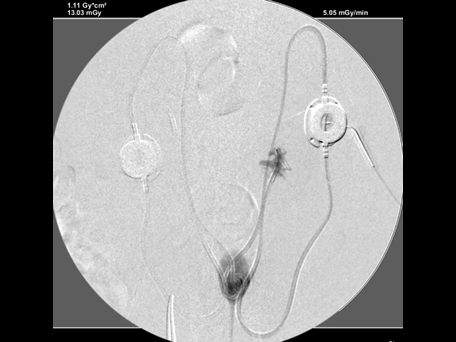

造影で漏れがないか何度も確認

必ず透視下にて漏れがないか何度も確認をします。 透視をしないとシステムや装着部分からの漏れが確認されたり、トラブルが考えられます。

実際、他院で装着して漏れがあるなどの相談をうけることがしばしばあります。

透視下にて実施すれば適切な位置に装着できます。

綺麗につければ感染や漏れもほとんどなく、経過はとても良好です。

透視下にて腎盂に入っていることを確認。

ここにカテーテルを装着していきます。

SUBシステムを設置しました。

漏れを確認して終了となりました。